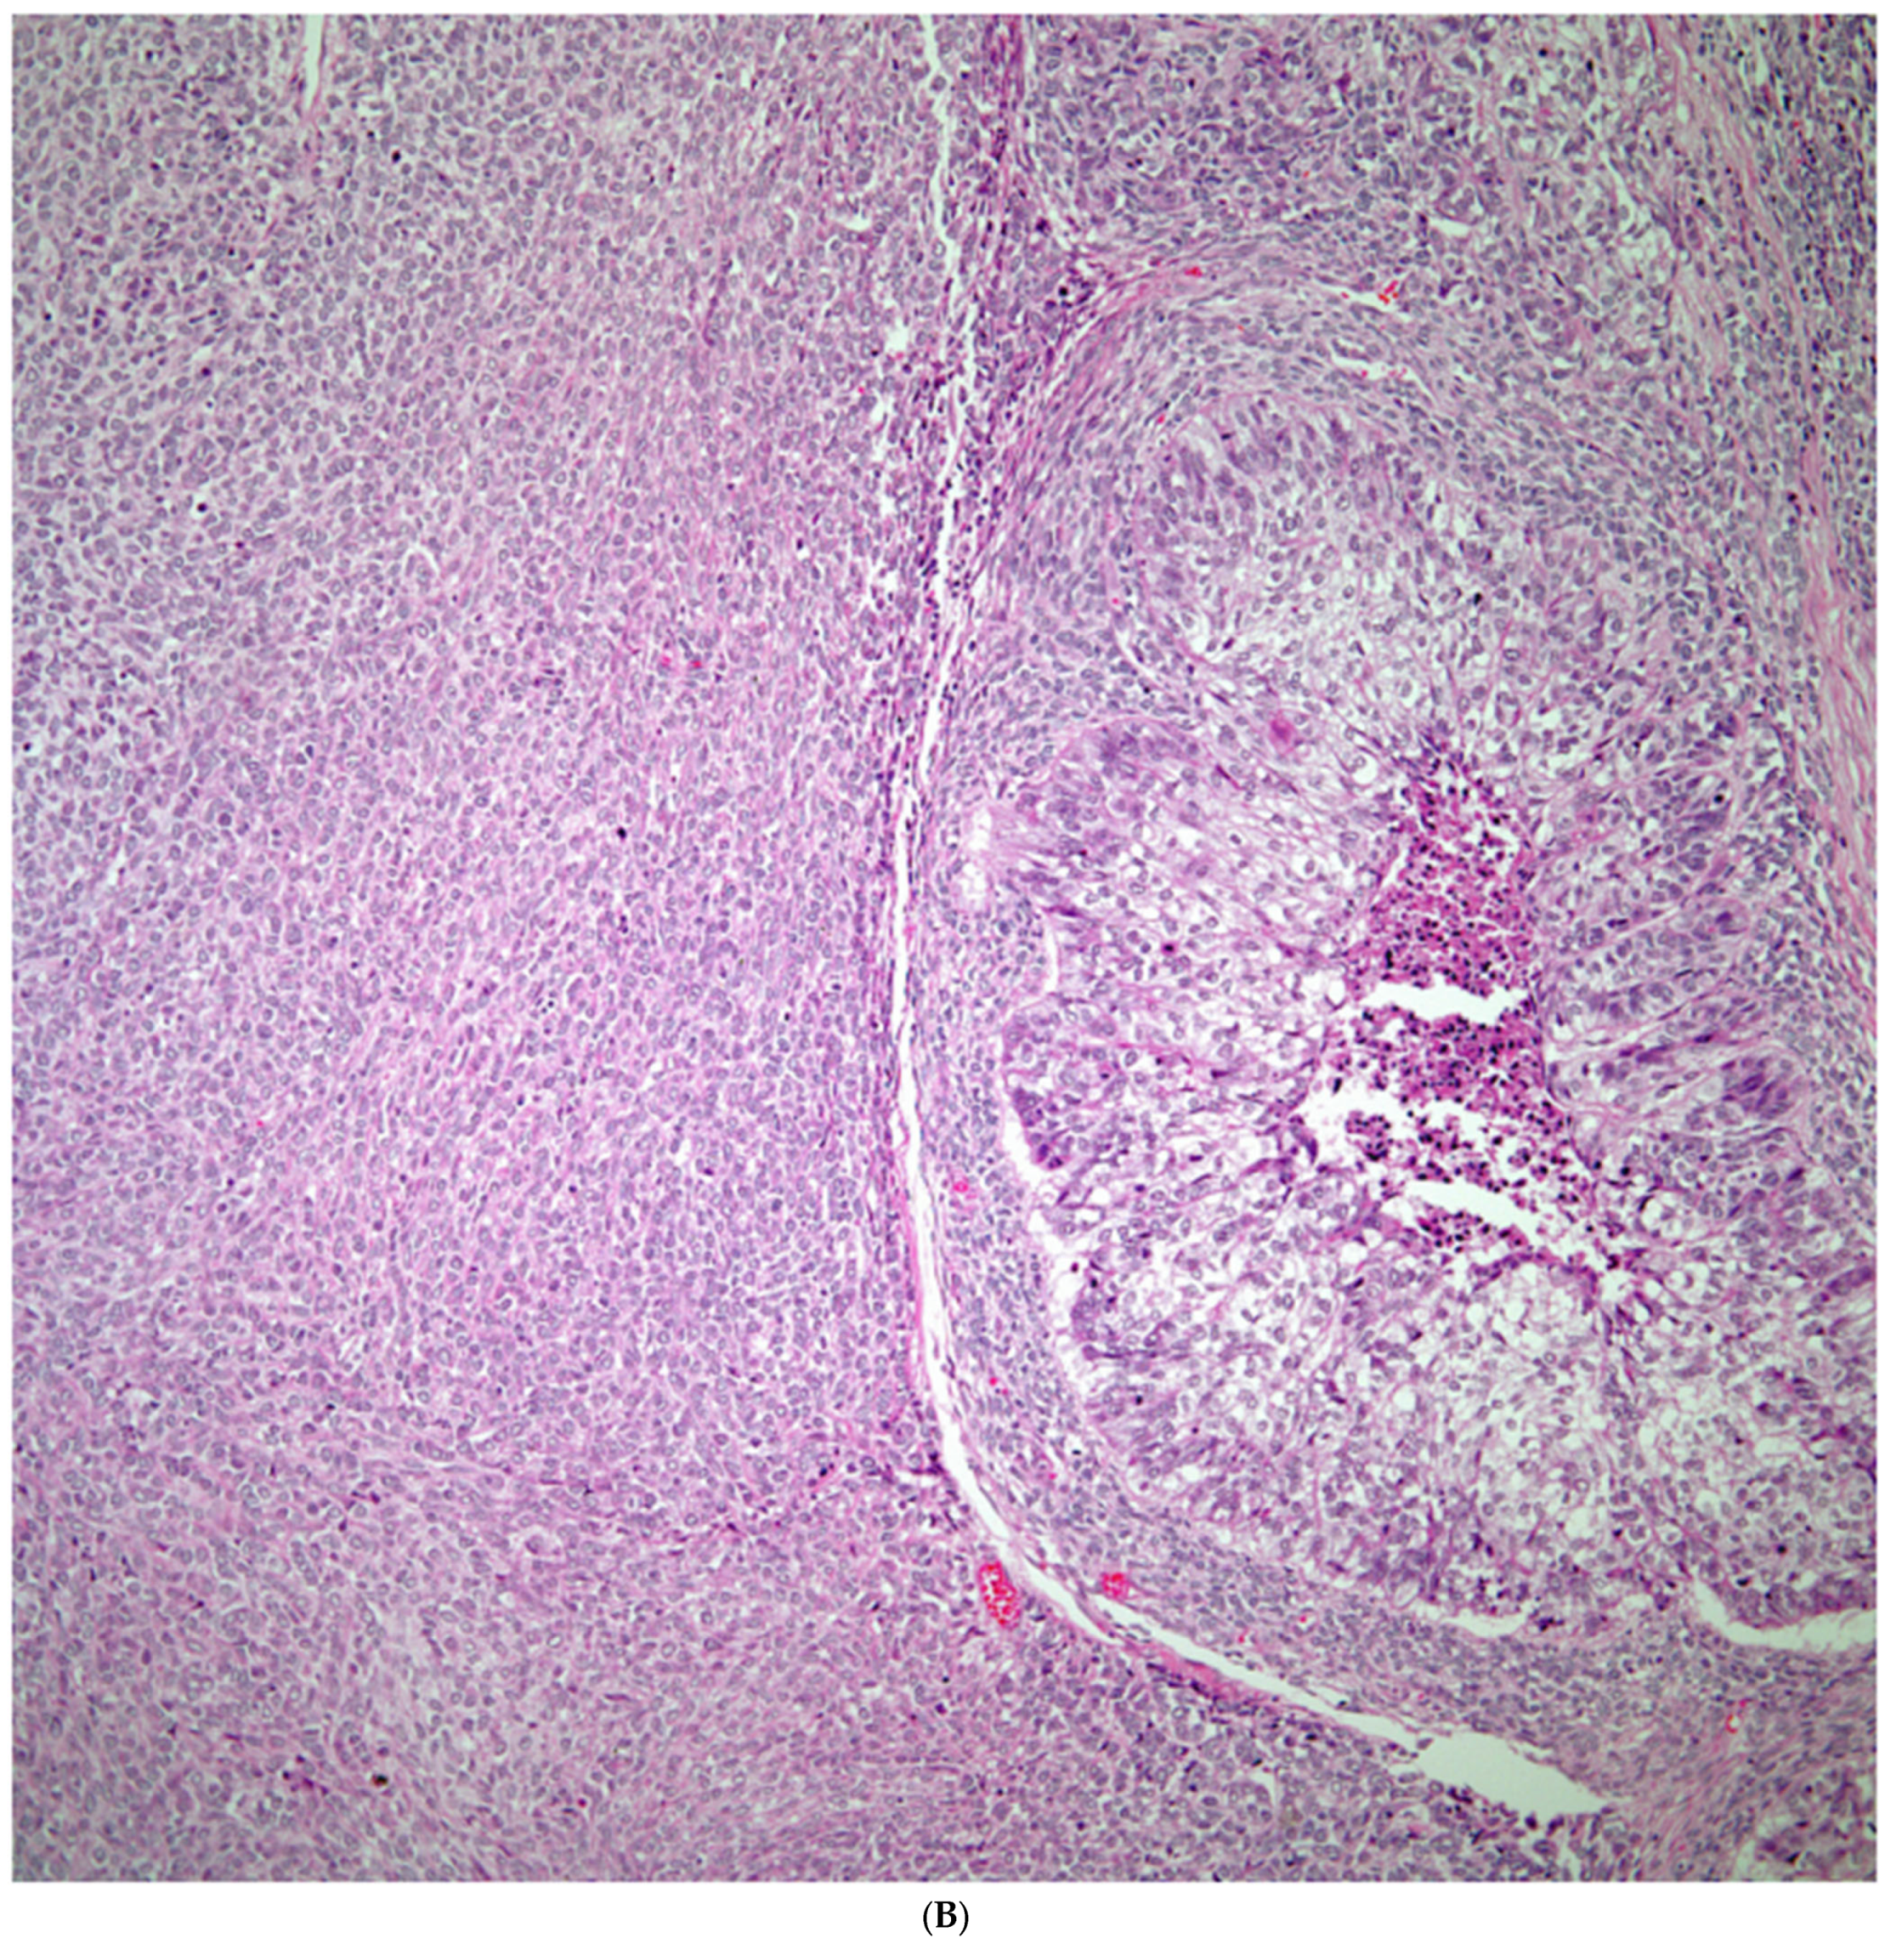

Sarcomatoid carcinomas: These tumors show a tightly packed spindle cell proliferation composed of slender cells with fusiform nuclei and inconspicuous nucleoli, replacing normal lung parenchyma. The tumors are well delimited but not encapsulated (Figure 1). Cellular atypia is variable and may show areas of mild to moderate to marked atypia. Mitotic figures also vary and may be inconspicuous or may be evident with the presence of atypical mitotic figures (Figure 2A,B). In high-grade tumors, the presence of necrosis and hemorrhage is prominent and is mixed with the neoplastic component. Important to recognize is that sarcomatoid carcinomas may be associated with areas of otherwise conventional non-small cell carcinoma such as adenocarcinoma or squamous cell carcinoma (Figure 3A,B). In addition, sarcomatoid carcinoma may also show the presence of bizarre giant cells admixed with the spindle cell component (pleomorphic carcinoma) (Figure 4).

Figure 3.

(A) Sarcomatoid carcinoma associated with areas of conventional adenocarcinoma; (B) Sarcomatoid carcinoma associated with areas of squamous carcinoma.